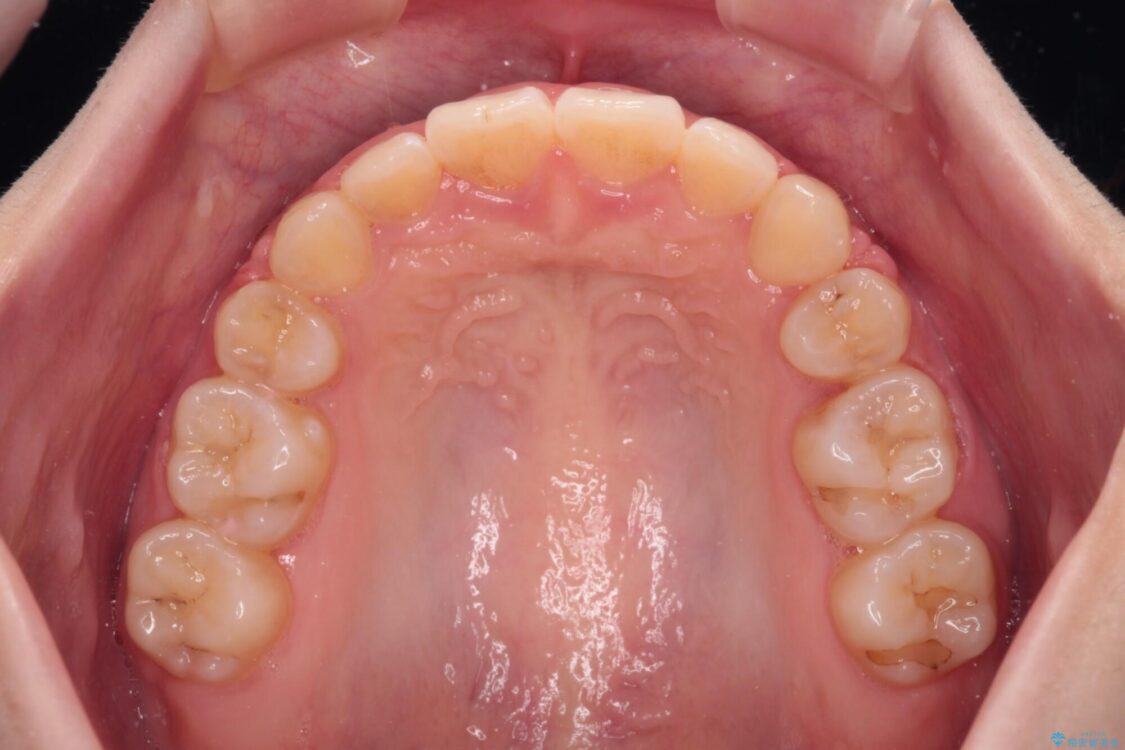

上下の前歯が突出しており、口が閉じにくいとのことで来院された患者様です。

上下前歯が著しく前突している状態であったので、上下左右の第1小臼歯4本を抜歯し、ワイヤー装置にて矯正治療を行うこととしました。

舌の突出癖により、前突になったと考えられたため、舌のトレーニングをしっかりと行うよう指導しました。

※写真にある上顎装置はメタルブラケットではありません。メーカー在庫都合などにより別の装置を使用しております。

舌の突出癖があり、前歯の移動量も多くなるため、治療期間は長くなると予想されましたが、13ヶ月という予定の半分程度の期間で終えることができました。